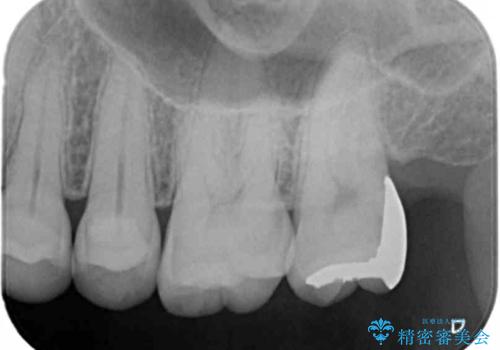

- 検査の結果、左上の一番奥の歯のさらに奥の面の深い位置に虫歯が潜んでいることを確認しました。

外から見えない位置であるため、セラミックよりも精度を上げることができるゴールド(PGAインレー)で修復していきます。

- 左上7 ゴールドインレー 77,000円費用は治療当時の料金となります

昔親知らずが埋まっていた場所にできてしまった虫歯であるためかなり深い位置に潜り込むような虫歯でした。

このような虫歯でも丁寧に処置することで問題なく適合の良いインレーを入れることができます。